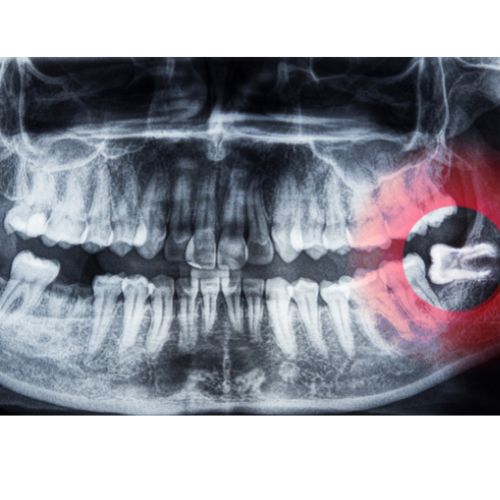

Digital dental x-ray technologies can identify cavities, and hidden dental structures such as wisdom teeth or foreign bodies, and bone loss. Digital x-rays also reveal certain bone quality information, prior to your plans on dental implants that may not be detected with a clinical visual examination. Learn More